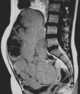

Dysgerminoma

A dysgerminoma is a type of germ cell tumor; it usually is malignant and usually occurs in the ovary. A tumor of the identical histology but not occurring in the ovary may be described by an alternate name: seminoma in the testis or germinoma in the central nervous system or other parts of the body. [Source: Wikipedia ]